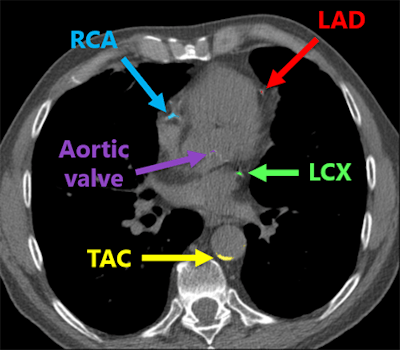

In all scans, manual annotations were performed for calcifications that were found in the left anterior descending artery (LAD) inclusive of the left main coronary artery, as well as the left circumflex artery (LCX), the right coronary artery (RCA), the visible part of the aorta, the aortic valve, and the cardiac valve. However, 16 (6%) of the scans had insufficient image quality and were excluded from the research project, Lessmann said. It took between five to 60 minutes to manually annotate each study.

Deep-learning algorithm correctly detected and labeled calcifications on a routine chest CT scan. All images courtesy of Nikolas Lessmann.This performance yielded a linearly weighted kappa of 0.82, indicating an "excellent" level of reliability, Lessmann said.